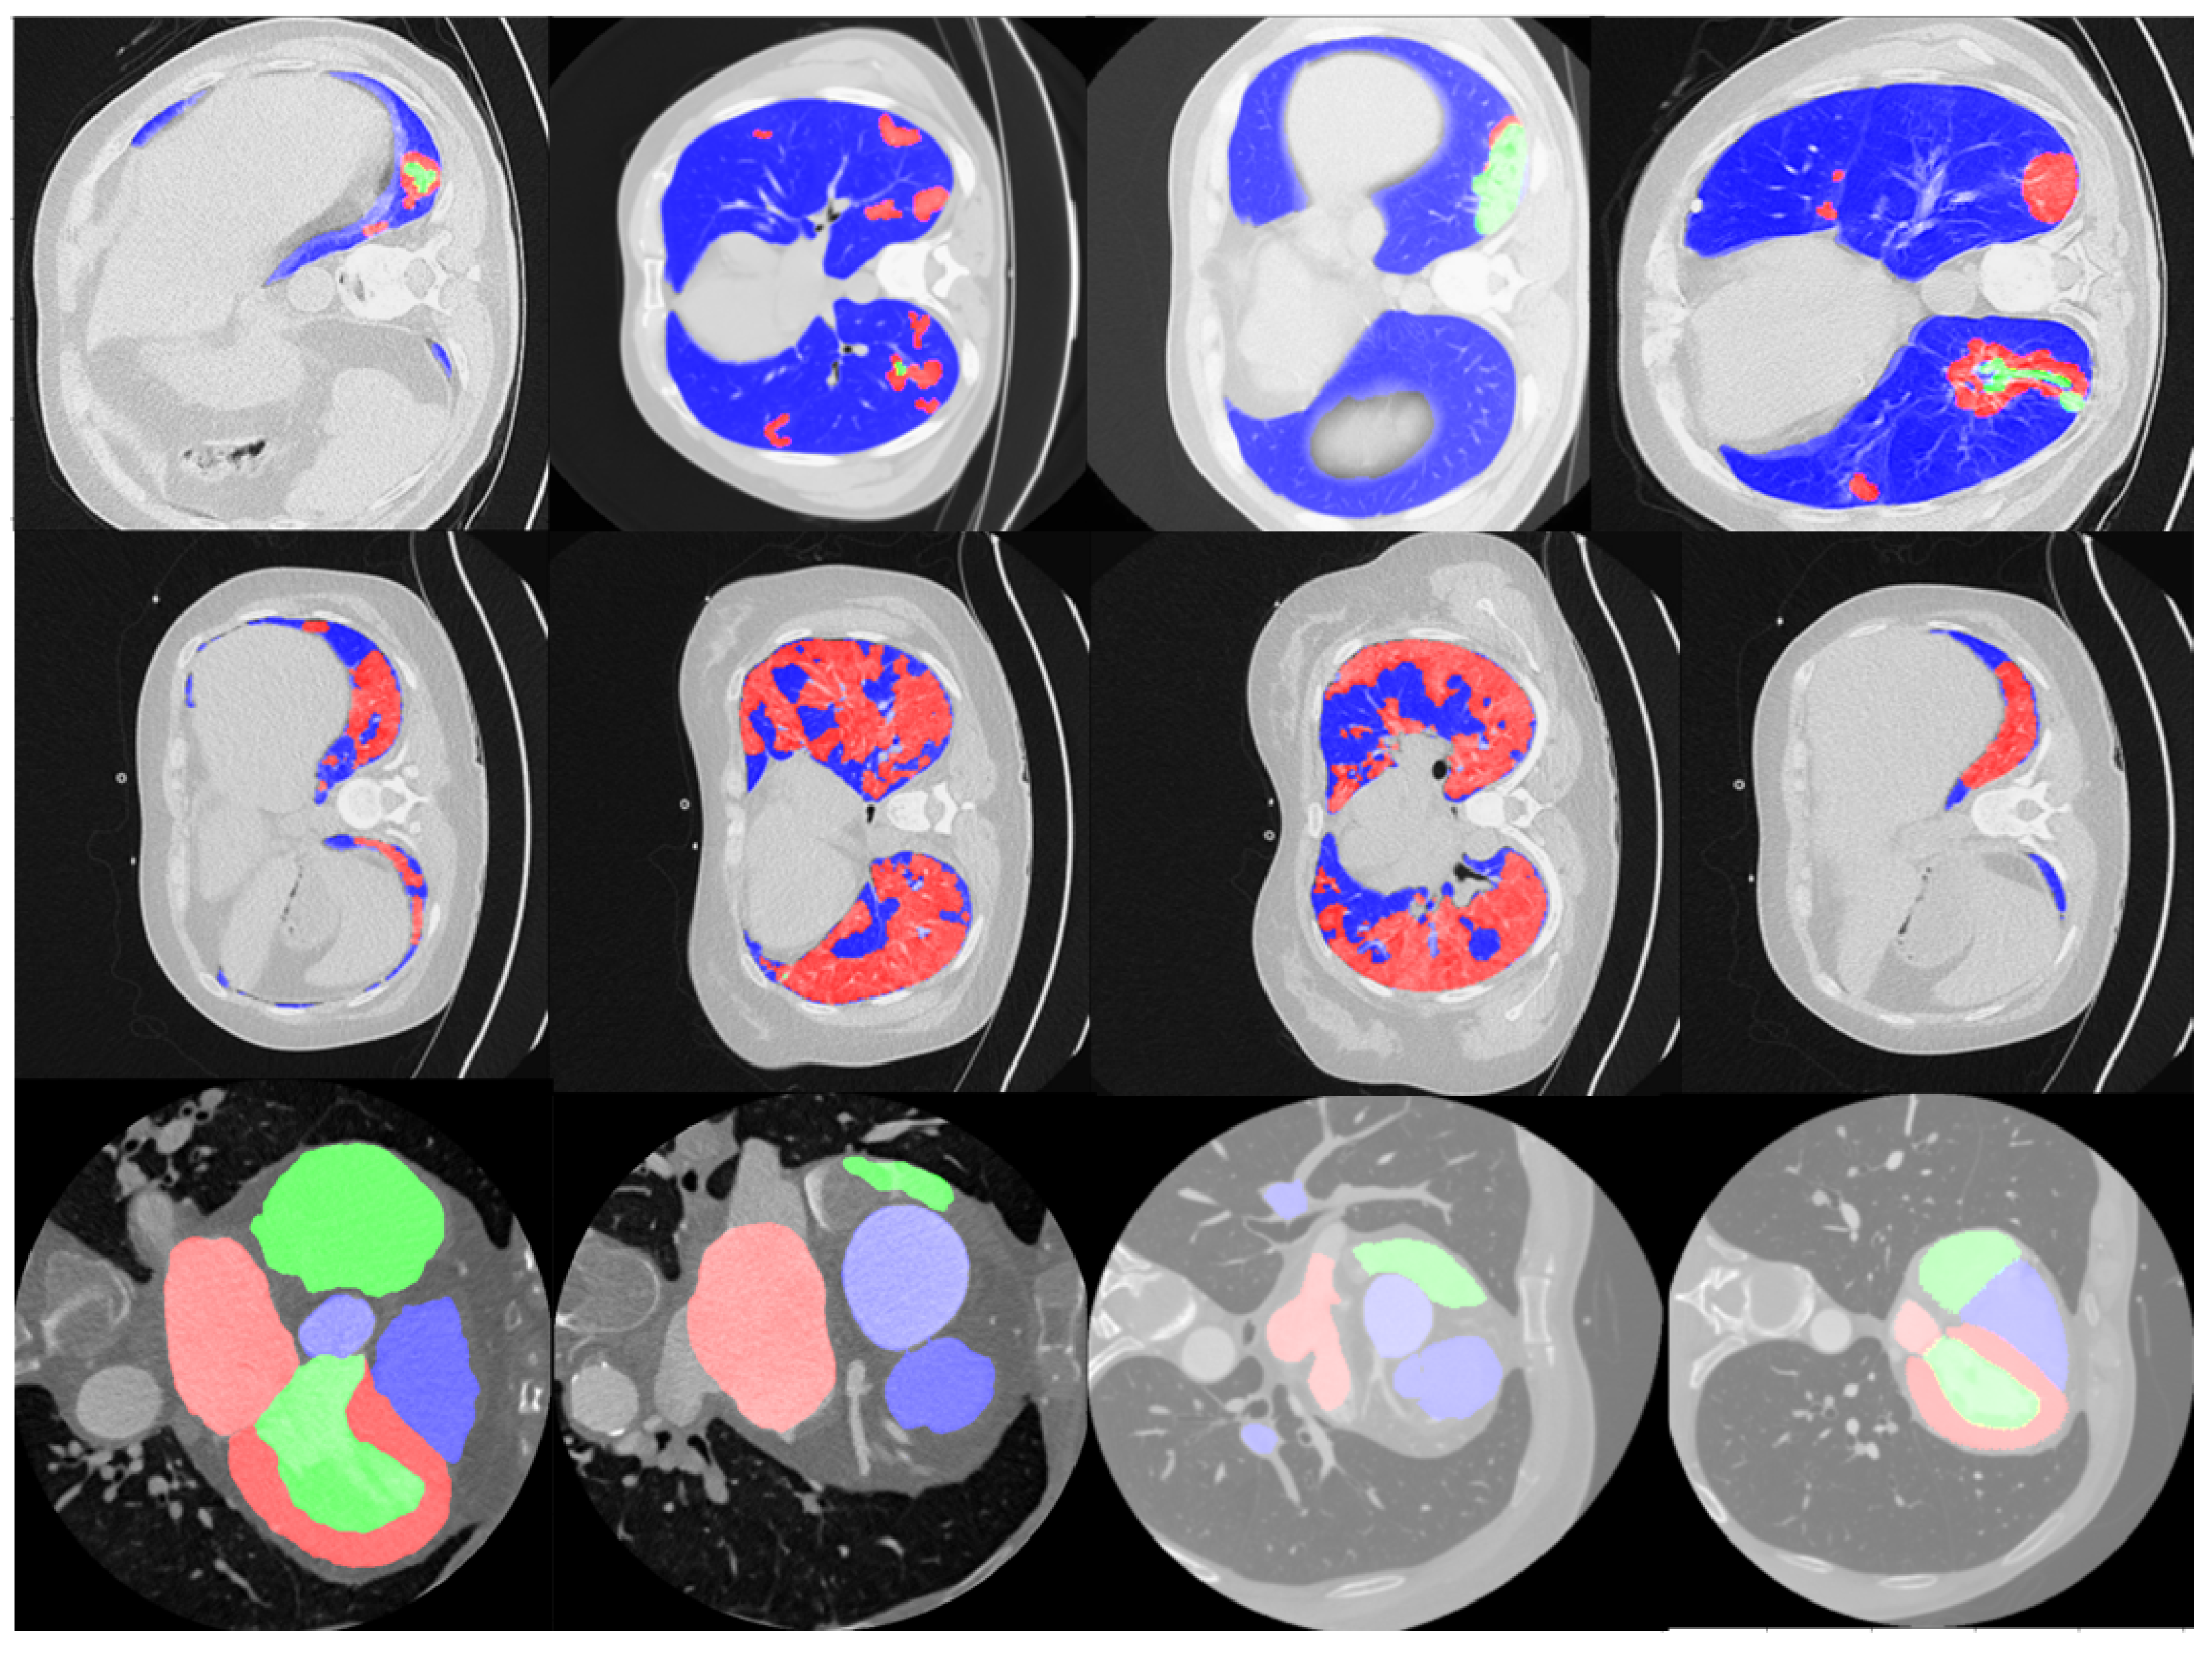

- The transfer learning performance analysis of the proposed model compared to existing Unet variants on multiple CT image stacks from Lung-CT (thoracic region) scans to Heart-CT regions. The NUMSnet model achieves up to 20% improvement in segmentation recall and 2–16% improvement in scores for multi-class semantic segmentation across image stacks.

3.1. Data: Lung-CT and Heart-CT Stacks

4.4. Transfer Learning for Heart-CT Images